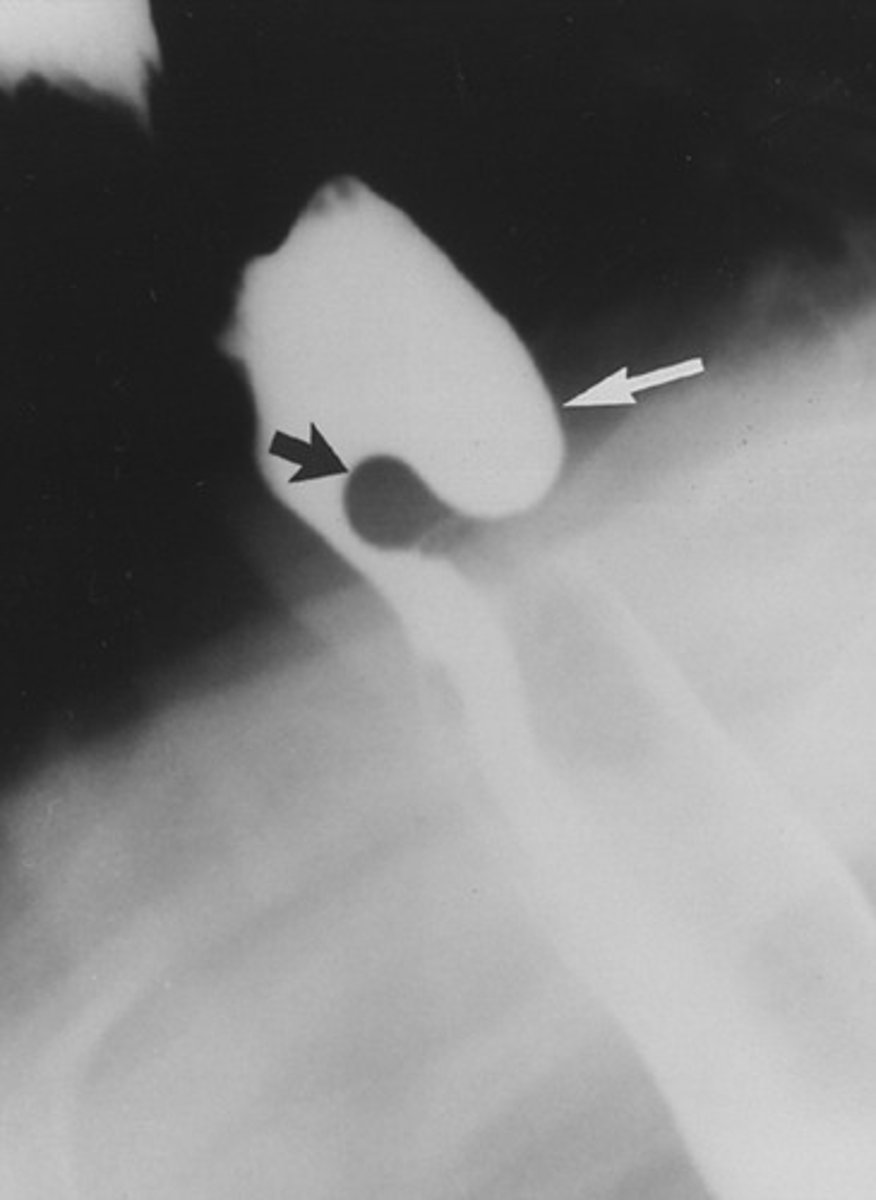

hypertrophied cricopharyngeal muscle